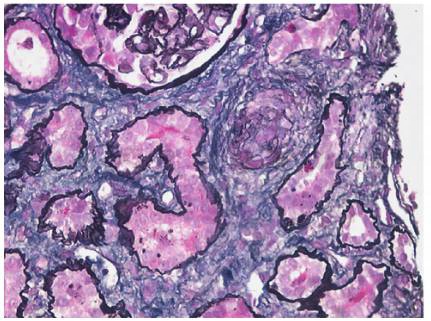

肾穿刺病理学检查(入院第7天):免疫荧光:均阴性。光镜:17个肾小球,肾小球系膜细胞和内皮细胞弥漫增生,基底膜节段性增厚伴假双轨征形成(图1),1个纤维性新月体形成;肾小管上皮细胞空泡及颗粒变性,多灶状及片状萎缩,多数红细胞管型,灶状再生;肾间质弥漫水肿,灶状淋巴和单核细胞及白细胞浸润;小动脉管壁增厚,内皮细胞肿胀;符合血栓性微血管病伴急性肾小管间质肾病。电镜:肾小球内皮细胞节段性增生,基底膜内疏松层增宽,上皮足突大部分融合(图2)。病理结果符合TMA肾损害合并急性肾小管间质肾病。

图1 妊娠相关血栓性微血管病:肾间质小动脉管壁增厚,内膜黏液变性,血栓形成(PASM×5 000)